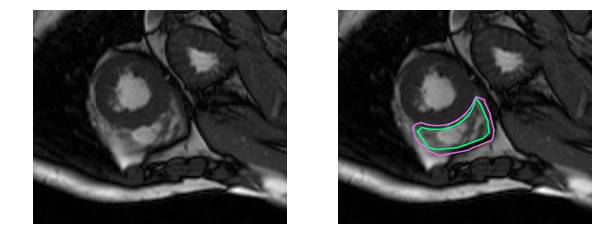

这是一个分割起来很容易的例子。这一个比较困难:

而这对于没有经过训练的眼睛来说完全是一个挑战:

事实上,与左心室相比,医生需要耗费两倍的时间来确定右心室的体积并生成结果。这项工作的目的是建立一个高度准确的右心室自动分割深度学习模型。模型的输出是*分割掩码*,即一个逐像素的掩码,用来表示某个像素是否是右心室的一部分或只是背景。